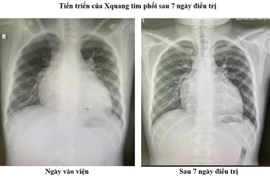

Bệnh nhi 11 tuổi bị suy tim cấp rất nặng, EF chỉ còn 18% vừa được Bệnh viện Đa khoa Xanh Pôn điều trị thành công.